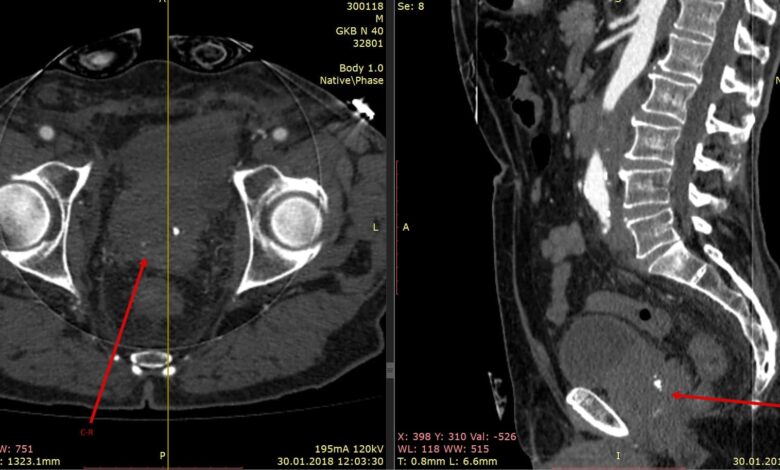

Компьютерная томография (КТ) грудной клетки является важным методом диагностики опухолей и других патологий легких и окружающих тканей. Это невероятно точное и информативное исследование, которое позволяет выявить заболевания на ранних стадиях и определить их характеристики.

С помощью КТ грудной клетки можно получить трехмерное изображение органов и тканей, что обеспечивает более детальное исследование, чем обычные рентгеновские снимки.

Одним из ключевых преимуществ КТ является возможность детектирования очень маленьких опухолей и изменений в тканях, которые могут остаться незамеченными на других видах обследований.

КТ также позволяет оценить степень распространения опухоли, наличие метастазов и возможные осложнения заболевания.